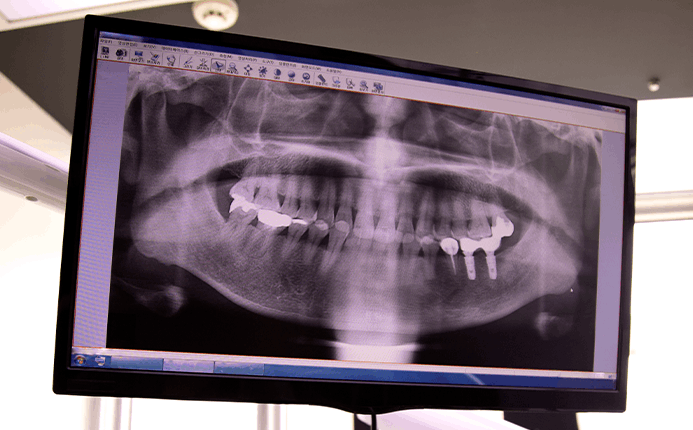

하지만 치조골이 부족하거나 잇몸에 염증이 심한 경우에는 발치후 즉시 임플란트가

어려울 수 있기 때문에 3차원 CT 촬영 등을 통한 정밀진단이 필요합니다.